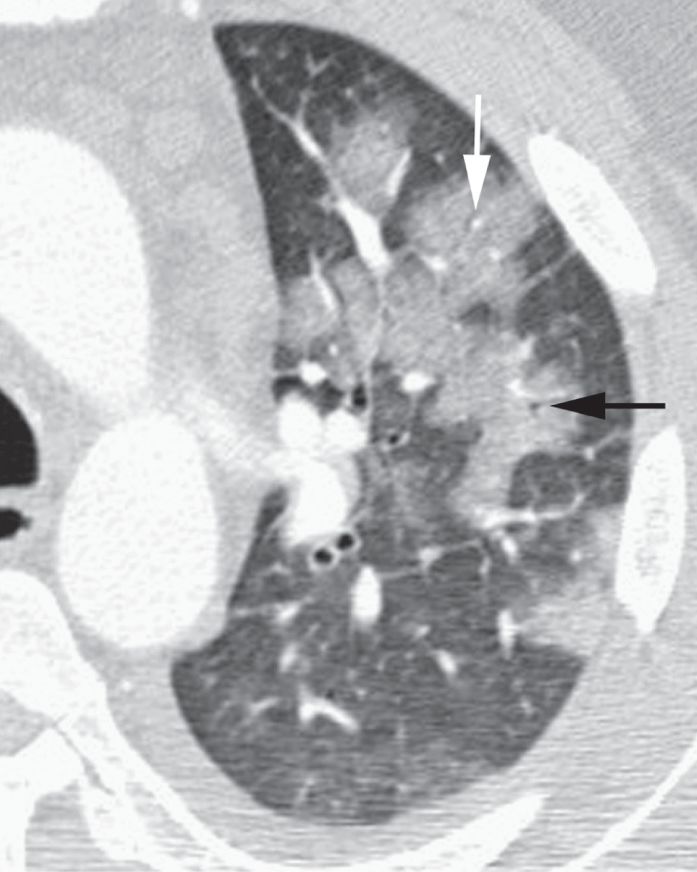

图2-2 实变:边界不清的,毛玻璃样致密影伴“肺泡充气征”

放大影像细节观察右肺下叶实变呈磨玻璃样边界不清的致密影,内含有小圆形透亮影,称为肺泡充气征,尽管与实际肺泡大小并不相符;B.右下叶肺炎患者胸部CT显示边界不清的磨玻璃样实变(白色箭头),实变区内小的局灶性透亮影(黑色箭头)为“肺泡充气征”

肺泡充气征

如果肺实变不融合,可以看到间杂小的局灶性透亮区,代表未受累的肺组织( 图2-2)。这些透亮区被称为“肺泡充气征”,但因为肺泡太小无法在X 线片上看到,这是一个误称。这些透亮区反映了不完全肺实变。